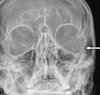

2

Q

A

left horizontal semi circular canal